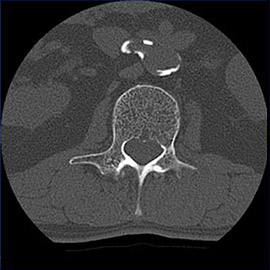

80列マルチスライスCT 検査 画像例

80列マルチスライスCTで撮影した画像

腹部

腹部(造影)

1スライスの腹部単純撮影画像から体脂肪面積や皮下脂肪面積を計測し、それぞれの蓄積を観察できます。